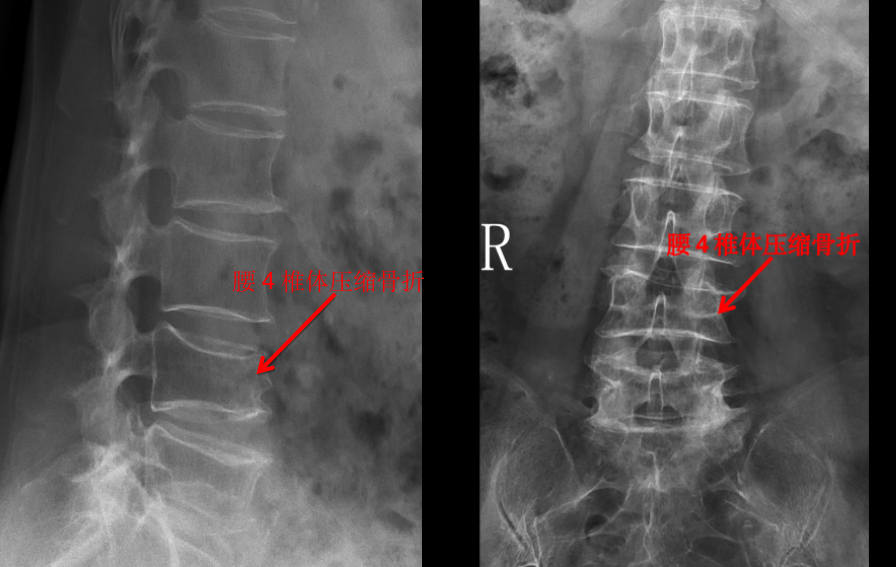

我们管 X 线检查叫 X 光片、照相或拍片。在 X 光片里,我们能看到脊柱有没有骨折,有没有骨质破坏,有没有脊柱侧弯、有没有骨质增生等。一些有经验的大夫,可以通过椎间隙高度的丢失判断椎间盘的退变程度。

但是对于大部分软组织病变如椎间盘、椎管内神经、有没有占位性病变等却无能为力。如果患者有压缩骨折,X 光片也无法判断是新鲜骨折还是陈旧骨折,这样也就无法定制下一步诊疗计划。

所以,X 光片的优点是廉价、检查快捷,缺点是对人体有辐射,组织显像有限,只能看骨头,不能看软组织。

一般来说,X 光片在脊柱外科里,属于一种基础检查或筛查,对绝大多数腰背痛的病人都适用。